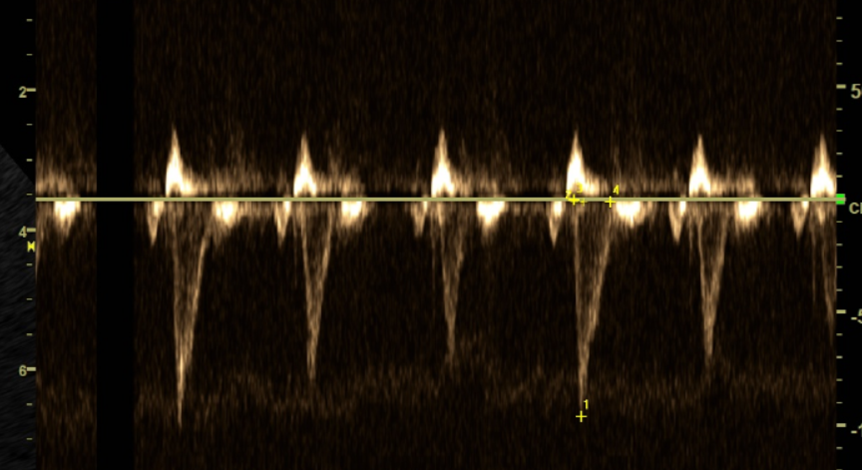

<초음파 검사 - LA/Ao와 LVIDdN이 매우 높게 측정>

초음파 검사에서 역시나

좌심방과 좌심실이 모두 오랜 기간의

부하로 인해 커져 있는것이 확인되었습니다.

<PA/Ao 비율이 1.5 정도로 주폐동맥이 확장>

<우심실 유출로의 AT(일종의 유출 속도)가 34.05ms정도로 짧음>

- 도플러 검사상 좌우 대칭이 아닌 뾰족한 모양을 나타냄

- PR velocity가 2.65m/s로 기준치인 2.5보다 높음